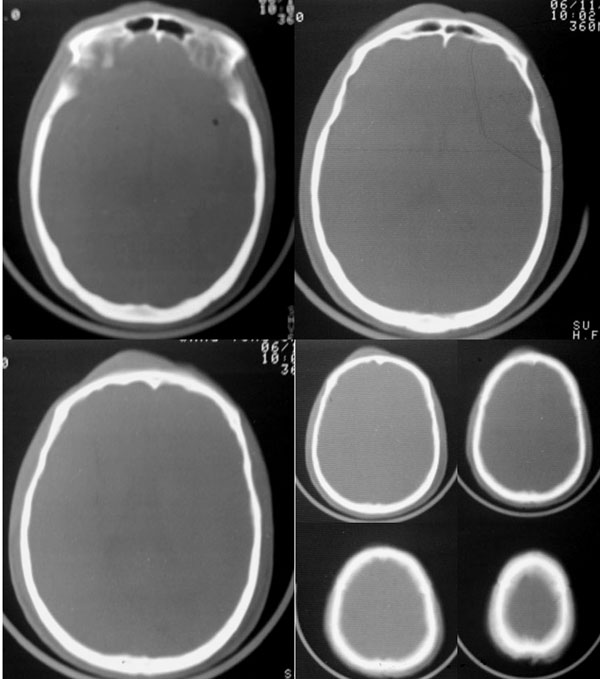

以下是引用dyqct在2006-11-9 15:04:00的发言:[br]左枕叶、双顶叶各见一处似三角形低密度区,边界尚清楚,无占位效应,累及皮质,白质侧未见灰质影。余所见未见异常。[br]考虑:1、脑软化灶;[br] 2、不支持脑裂畸形,该病病变区两侧应有灰质带——即灰质异位,临床上常有顽固性颠痫。当然了脑软化灶也偶会出现颠痫。

以下是引用守望可可西里在2006-11-9 15:06:00的发言:[br][br] 1.左侧枕叶低密度与侧脑室相通,考虑开唇型脑裂畸形。[br] 2.双侧顶叶低密度考虑局部脑沟异常扩大,发育问题。